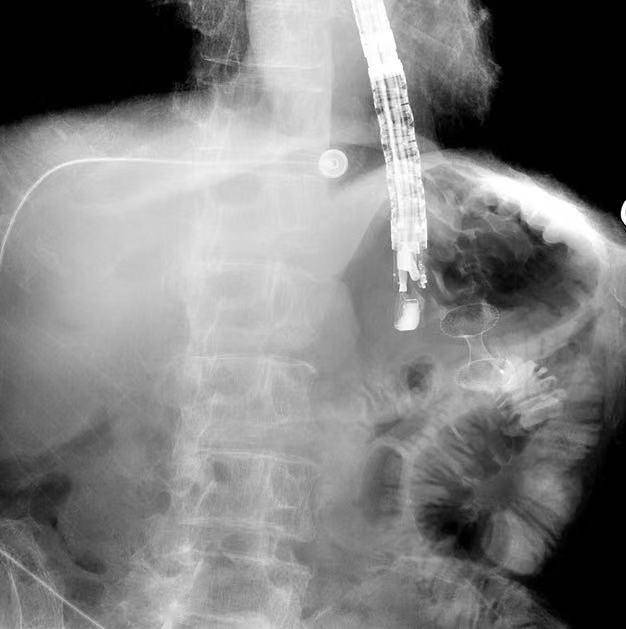

术中成功放置支架

支架的两端如同伞面一样,在胃腔和空肠腔内打开,瞬间将胃壁和空肠壁紧紧拉拢在一起,一个全新的旁路就此建立。

术中影像